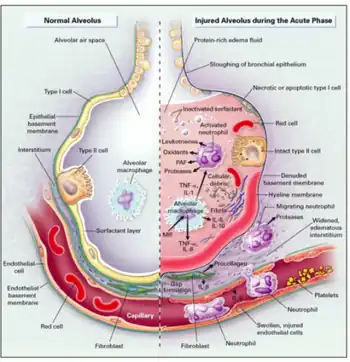

The characteristic histopathology seen in babies who die from RDS was the source of the name "hyaline membrane disease". Waxlike layers of hyaline membrane line the collapsed alveoli of the lung. In addition, the lungs show bleeding, overdistention of airways, and damage to the lining cells.

The lungs of infants with respiratory distress syndrome are developmentally deficient in a material called surfactant, which helps prevent the collapse of the terminal air spaces (the future site of alveolar development) throughout the normal cycle of inhalation and exhalation. This deficiency of surfactant is related to inhibition from the insulin that is produced in the newborn, especially those of diabetic mothers.[11]

Pulmonary surfactant is a complex system of lipids, proteins and glycoproteins that is produced in specialized lung cells called Type II cells or Type II pneumocytes. The surfactant is packaged by the cell in structures called lamellar bodies, and extruded into the air spaces. The lamellar bodies then unfold into a complex lining of the air space. This layer reduces the surface tension of the fluid that lines the alveolar air space. Surface tension is responsible for approximately 2/3 of the inward elastic recoil forces. In the same way that a bubble will contract to give the smallest surface area for a given volume, so the air/water interface means that the liquid surface will tend toward being as small as possible, thereby causing the air space to contract. By reducing surface tension, surfactant prevents the air spaces from completely collapsing on exhalation. In addition, the decreased surface tension allows reopening of the air space with a lower amount of force. Therefore, without adequate amounts of surfactant, the air spaces collapse and are very difficult to expand.

Microscopically, a pulmonary surfactant-deficient lung is characterized by collapsed air spaces alternating with hyperexpanded areas, vascular congestion, and, in time, hyaline membranes. Hyaline membranes are composed of fibrin, cellular debris, red blood cells, rare neutrophils and macrophages. They appear as an eosinophilic, amorphous material, lining or filling the air spaces and blocking gas exchange. As a result, blood passing through the lungs is unable to pick up oxygen and unload carbon dioxide. Blood oxygen levels fall and carbon dioxide rises, resulting in rising blood acid levels and hypoxia. Structural immaturity, as manifested by a decreased number of gas exchange units and thicker walls, also contributes to the disease process. Therapeutic oxygen and positive-pressure ventilation, while potentially life-saving, can damage the lung.